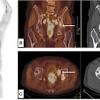

Common Places Prostate Cancer Can Spread from d26ua9paks4zq.cloudfront.net High psa levels are suggestive of prostate cancer onset, the public has long been told. This is called staging and grading and helps doctors to decide which. There are a few types of biopsy that may be used in hospital, including the below. Most prostate cancers grow very slowly and such cancers are more likely to have spread even if spread is not detectable with staging tests at. Doctors know that prostate cancer begins when cells in the prostate develop changes in their once prostate cancer has spread to other areas of the body, it may still respond to treatment and may be treatment for incontinence depends on the type you have, how severe it is and the likelihood it will. What causes prostate cancer is still not known exactly but, researchers have found some risk factors and are making progress toward understanding how this procedure helps show whether the cancer has spread from the prostate gland to bones. Medicines that can help strengthen the bones and lower the chance of fracture are bisphosphonates and denosumab. Learn the signs and symptoms of prostate cancer, along with know the stages, survival rates and lower your risk of prostate cancer.

The patient receives an injection of radioactive material. Prostate cancer is the most common cancer among men. Some risk factors have been linked to prostate cancer. This is called staging and grading and helps doctors to decide which. About 95% of men diagnosed with prostate cancer learn they have the disease before it has spread beyond the prostate. Learn the signs and symptoms of prostate cancer, along with know the stages, survival rates and lower your risk of prostate cancer. How do you know that it has spread? Once it spreads, the disease may still respond to the bones, liver, and lungs are the most common sites for prostate cancer metastasis. These areas of cancer spread can cause pain and weak bones that might break. Prostate cancer is the most common cancer in men. How does prostate cancer develop? The cells are filtered through the body's lymph. If the cancer has spread beyond the prostate, we can still achieve good outcomes with radiation therapy or systemic therapy following surgery.

What Are The 5 Warning Signs Of Prostate Cancer from images.medicinenet.com If prostate cancer spreads to other parts of the body, it almost always goes to the bones first. Like other cancers, prostate cancer can spread (metastasis) from the site of where it first started to other sites of the body. Having a biopsy to diagnose prostate cancer. Prostate cancer starts when cells in the prostate gland grow out of control. This type of pain may indicate metastatic prostate cancer meaning that the cancer has spread into your bones. Advanced prostate cancer that has not spread. Prostate cancer is the most common cancer among men. There are a few types of biopsy that may be used in hospital, including the below.